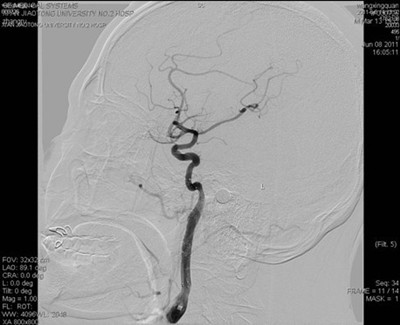

图4 侧位片:左侧颈内动脉血管内狭窄部位支架成形术后,血管通畅

患者送入我院时意识模糊,右侧肢体完全不能移动,不能言语,我院神经内科按照脑梗死应急预案,通过急性脑梗死绿色通道立即行头颅CT排除脑出血。考虑脑梗死,但病灶尚未显示,有急诊动脉介入治疗的指证和时间。吴海琴主任和张桂莲副主任立即向家属谈病情并介绍介入治疗的利弊,同时展淑琴副主任医师和卜宁及孙宏主治医师指导完成术前各项准备工作并加用基础治疗。家属了解病情后签字同意介入治疗。吴海琴主任、张桂莲副主任、张茹副主任医师立即在祁小江技师、赵菊凤护士的配合下给患者行脑血管造影,造影见左侧颈内动脉内有异常混杂密度团块影,并局部重度狭窄,远端血管血供极差,考虑血栓形成所致狭窄。虑及动脉溶栓有可能使血栓脱落,栓塞远端血管,遂在保护伞的保护下给局部狭窄部位安放2枚支架,把血栓压住贴壁,使狭窄的颈内动脉基本恢复正常,远端血供恢复,患者意识清楚,右侧肢体能够在床头移动。此时距离患者发病仅4小时。今晨患者右侧肢体能够抬离床面并对抗阻力,能连续说出数个单词。